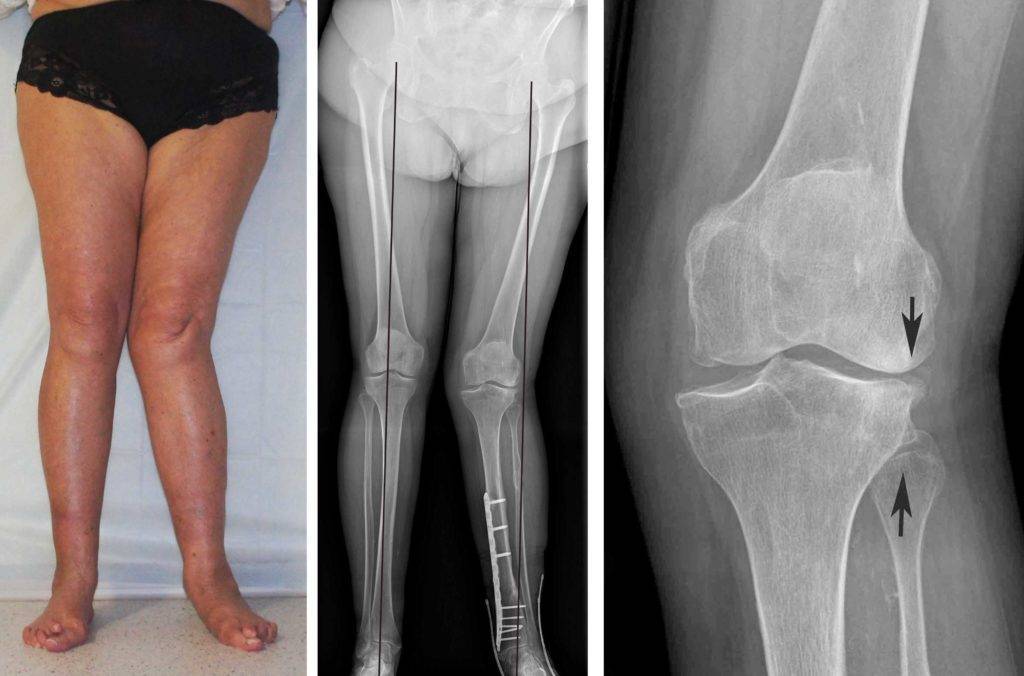

При обнаружении искривления ног ребенка следует показать ортопеду. Врач осмотрит ребенка и направит на рентген суставов. Рентгенологическое исследование дает полную картину заболевания: большеберцовая кость искривлена, суставная поверхность кости скошена под углом, кортикальный слой по внутренней поверхности кости утолщен и др. В дифференциальной диагностике обычно нет необходимости. Дополнительно для исследования хрящевой ткани может быть выполнена компьютерная томография коленного сустава, для исследования мягких тканей – МРТ коленного сустава.

Важной задачей при постановке правильного диагноза является определение причины искривления, поскольку кривизна голеней является вторичной патологией. Нужно провести дифдиагностику заболевания Блаунта от рахита. Для этого ребенку назначают анализ крови, по которому определяют кальций, фосфор, щелочную фосфатазу

Если показатели в норме, то диагноз выставляется по результатам объективного осмотра и проведения рентгенологического исследования. Врач расспрашивает родителей о времени появления первых симптомов, клинических проявлениях, возрасте ребенка, наследственном предрасположении. Визуально определяются следующие симптомы:

- видимое укорочение конечностей;

- характерное искривление в коленном соединении наружу или внутрь;

- снижение мышечного напряжения;

- развитие плоскостопия.

Рентген показывает определенные изменения:

- Образуется клювовидное деформирование большеберцовой кости. Патология локализуется в верхнем участке метафиза или области между ним и эпифизом.

- Поверхность суставного сочленения кости изогнута внутрь и скошена. Высота эпифиза изнутри втрое ниже нормального размера, наблюдается краевое дробление.

- Ростковая зона изнутри расширяется, костные пластинки с нечеткими границами. У подростков диагностируют преждевременно закрытую зону роста кости.

- Из-за ротации проекции мало- и большеберцовой костей на снимке накладываются друг на друга.

Патологический процесс затрагивает не только кости, но и сухожилия, мышечный слой. Для определения степени повреждения мышечных и связочных волокон применяют КТ или МРТ. С помощью томографии послойно исследуют ткани, выявляют состояние костей и хрящей.